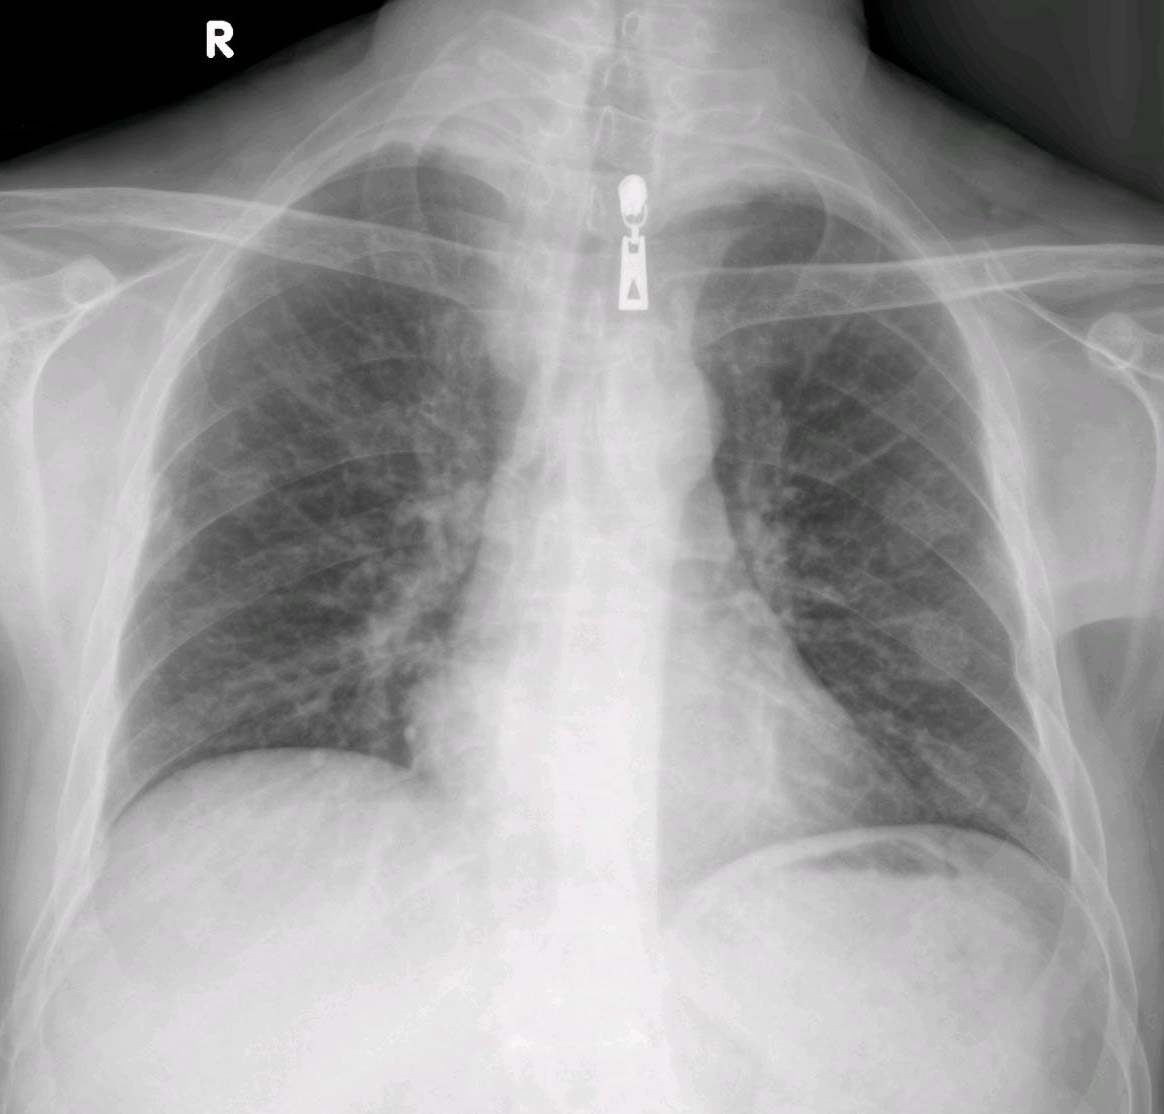

15天前外伤,现胸部不适!片子请帮看看!

考虑:1、左侧3-5前肋骨折;

2、右侧第8肋腋侧骨折;

3、必要时请做ct进一步检查。

左侧胸廓腋缘多发性肋骨折,象是陈旧性的。

两侧肺野内亦可见多个类似小块状影,建议作ct检查排除肺部新生物可能。

是不是湿肺吸收不全,机化所制的含铁血黄素结节,还有请大夫一定要注意患者的年龄及病势的提供,要不然真的很难诊断,

1多发肋骨骨折

2机化性肺炎可能

双肺散在的结节状密度灶,我觉得不是骨痂,所以我考虑是肺转移.